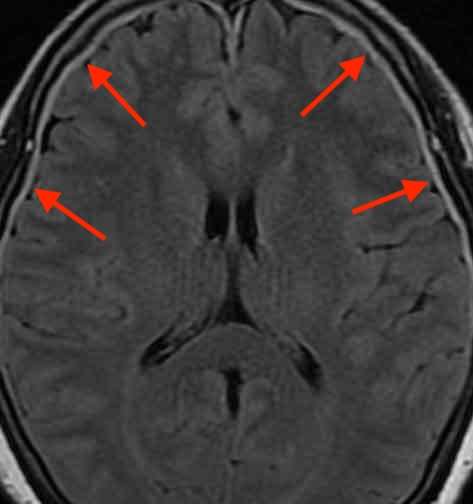

頭部MRI検査を行いました。

すると、脳の周囲を囲む白い部分が写っています。頭蓋骨と脳の間に硬膜という硬い膜がありますが、通常は薄いため写りません。つまり、硬膜が厚くなっており、硬膜肥厚という状態になっています。

脳脊髄液減少症という髄液が減って頭痛を起こす状態があります。硬膜は脳から脊髄までを包んでおり、通常は脊髄周囲の硬膜に穴があいて髄液が漏れるために生じます。硬膜肥厚は、内側から硬膜が引っ張られる事で生じます。

この方の場合には、調べた限り硬膜の穴は見つかりませんでした。しかし、髄液が漏れていなくても脳脊髄液減少症は起きることを示す文献はあります。2)

低血圧だけで脳脊髄液減少症をきたすという根拠はありませんが、、慢性的な低血圧と脱水のために髄液が作れなくなり、脳脊髄液減少症の症状を悪化させる可能性があると考えられます。